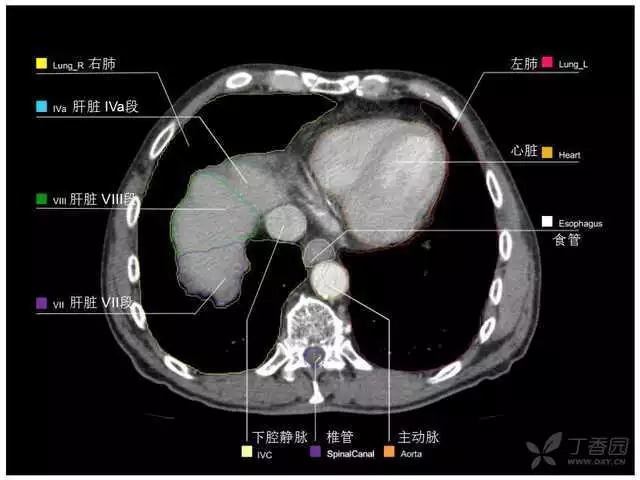

腹部肝脏高清CT断层的图谱

全腹部高清CT图谱,淋巴结彩色图谱,血管解剖图谱大汇总!

超声肝脏分叶及分段

肝脏分段和基本解剖学标志